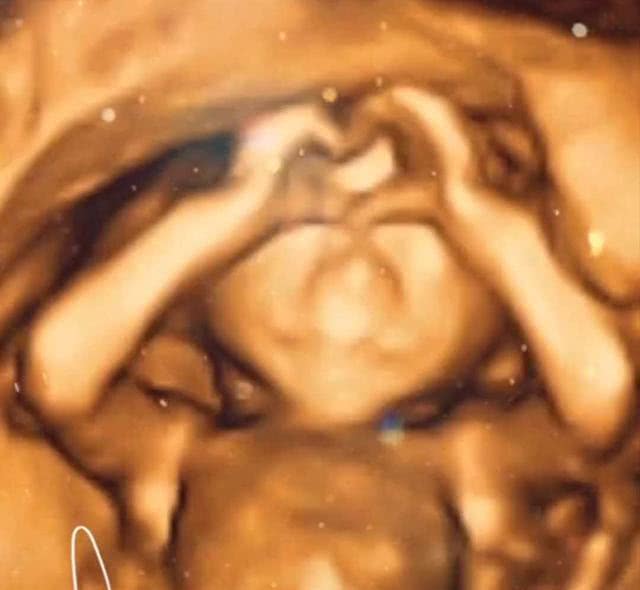

当孕妈到了孕22周—26周的时候,医生往往会建议孕妈做四维彩超,用以确定胎宝宝有没有畸形。大多数孕妈也会听从医生的建议,毕竟这将关乎到宝宝的未来。今天要说的这位妈妈就处在这个孕周,于是在老公与儿子的陪同下,孕妈开始了新一轮的产检。虽说胎宝宝不怎么配合产检,但是在妈妈与医生多次努力之下,还是顺利完成了这次产检。而当爸爸与大宝看到B超单时,两人就有些愣神了。

医生在拿到B超单子后会进行细致的查看,然后根据具体的情况给予孕妈合理的建议。就在医生认真查看B超单子时,爸爸与大宝也在一旁认真打量着,而B超单子上的图像让两人感到惊疑不定。原来产检时在给胎宝宝“拍照”的那一刻,宝宝用两只小手比了一个心形。所以爸爸与大宝感觉这是小宝在“隔空示爱”,妈妈对此也是感到很温馨,暗想自己这次怀的可能是一个小人精。网友们在看了这样的产检结果后也是感觉有些不可思议,纷纷留言点评。